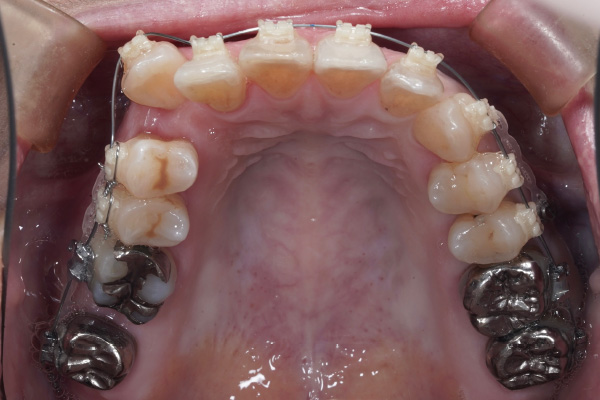

⚫︎主訴:八重歯を治療したい。前歯が咬んでないのを治療したい。

⚫︎前歯が咬んでいない

この症例の場合も、4ヶ月→8ヶ月で目に見える変化がありました。